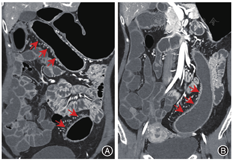

与结肠型CD相比,UC患者的病变更多表现为连续性分布(80%比57.5%,P = 0.03)、肠壁呈环周均匀性增厚(77.5%比47.5%,P = 0.006),较少出现肠周炎性渗出(20.0%比67.5%,P<0.001)及肛瘘(10.0%比57.5%,P<0.001),差异均有统计学意义。结肠型CD病变肠壁厚度大于UC患者[(9.5 ± 3.4) mm比(8.1 ± 2.2) mm,P = 0.024],更多表现为不同部位的严重程度不一致(75.0%比45.0%,P = 0.006),差异均有统计学意义,见图1,图2,图3,图4。两组患者其余影像学特征差异无统计学意义(P均>0.05)。见表3。

与UC相比,结肠型CD更多表现为病变节段性分布、非对称性肠壁增厚,厚度多厚于UC,肠周炎性渗出及肛瘘也更加常见,多变量回归模型也提示肠周炎性渗出、肛瘘是诊断结肠型CD的有效预测因子。多节段性病变是CD的典型影像学表现,而UC患者更多表现为病变连续性分布,与既往报道的一致[15]。另外,结肠型CD患者以非对称性肠壁增厚为主,提示即使位于同一部位的病变,CD患者仍具有跳跃性的趋势,从而表现为影像学上单一节段的肠壁厚薄不均匀。这同样解释了结肠型CD患者在不同部位表现为炎症反应程度不一致的可能原因,而UC患者则更常出现结肠病变相一致的影像学表现。然而,进一步多因素回归分析显示,节段性病变与非对称病变并不能作为诊断结肠型CD的独立预测因子。在肠壁厚度上,结肠型CD患者厚于UC患者,我们认为这与CD表现为累及肠壁全层的透壁性炎症相关,除黏膜层受累之外,黏膜下层炎性水肿也常常同时出现,更有甚者累及肌层之外。而UC仅累及肠壁的黏膜层,病变浸润深度往往表浅,造成了两者影像学上的厚度差异,虽然多因素回归模型显示肠壁增厚没有显著差异(P = 0.051),但肠壁厚度越大,诊断结肠型CD仍具一定的优势比。Ellrichmann等[16]通过超声内镜比较UC与CD的结肠病变厚度,证实了CD黏膜下层厚度高于UC(P = 0.0001),CD平均肠壁厚度稍高于UC,但两者之间差异无统计学意义(P = 0.06)。本研究中,结肠型CD常伴有肠周炎性渗出,而UC患者少见,这或许依赖于两者在病理上累及肠壁的深度及层次有所不同,从而导致继发肠周炎性渗出改变的差异。肠周炎性渗出的出现明显提高了诊断结肠型CD的价值,这也是多因素回归模型中诊断结肠型CD的重要预测因子。另外,结肠型CD患者有50%以上会合并肛瘘,而UC少见,肛瘘是本研究中回归模型的关键预测因子,具有高优势比,其中的具体机制尚不明确,但肛瘘的出现对结肠型CD的诊断具有重要的参考价值。这也提示我们,IBD患者在行腹部检查时,放射医师应尽量覆盖肛管的扫描,这将进一步有助于临床诊断。